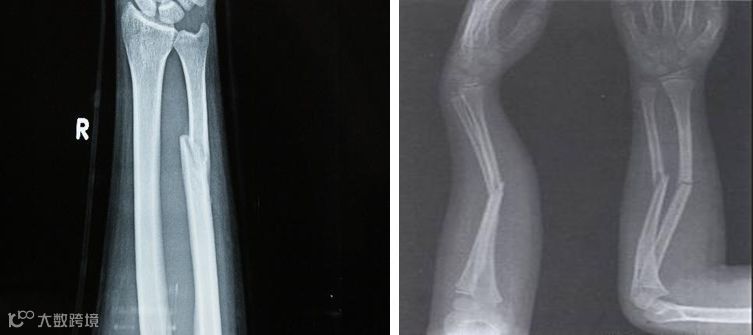

3、尺桡骨骨折

功能锻炼方法:

固定后即可做伸屈指、掌、腕关节活动,患肢做主动肌肉收缩活动。

肩、肘关节的活动同肱骨干骨折。骨折愈合后的锻炼:骨折愈合后,增加前臂旋转活动及用手推墙动作,使上、下骨折端产生纵轴挤压力。